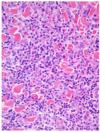

MDx

Ulcerative/Exudative dermatitis

MDx

Neutrophilic dermatitis/folliculitis